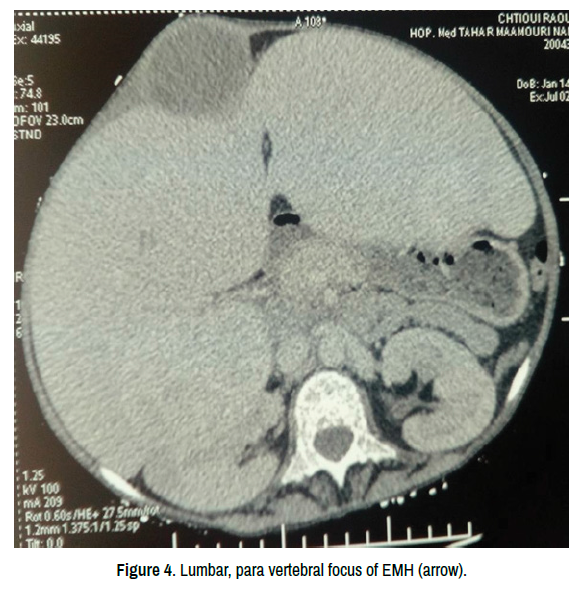

On inspection, the girl, with a stature and weight delay (-2 percentiles), was feverish at 38.4 °C. His abdomen was distended with a left costal scar in connection with splenectomy and shiny skin. She had an abdominal mass, ten centimeters above the umbilicus, right lateralized (Figure 2), sensitive and fluctuating. The palpation also revealed homogeneous hepatomegaly at 14 cm. Abdominal CT scan showed the hepatomegaly with 2 intra hepatic masses, a lumbar para spinal formation and the parietal collection with heterogeneous appearance (Figures 3-5). The biological assessment revealed a hyperleukocytosis with a white blood cells count of 15000/mm3 and elevation of CRP level to 120. It was also a hypo chromic, microcytic anemia (hemoglobin: 5.8 g/100mil) requiring a new phenotype blood transfusion. Since the age of 5 years, the patient had an iron chelation therapy but never had erythropoietin. The parietal abscess was flattened and the anatomy-pathological examination of a fragment of tissue taken at this level showed an inflammatory necrosis with foci of megakaryocytes and erythroblasts suggestive EMH. In front of the anamnesis (Foci of EMH at the macroscopic aspect of the spleen), the clinical context (severe chronic anemia and hepatomegaly), the imaging features and the anatomy pathological data, we concluded to EMH for the intra-abdominal foci with a probable cutaneous location.

clinical-case-reports-vertebral-focus

Figure 4. Lumbar, para vertebral focus of EMH (arrow).

Figure 5. The same aspect: Lumbar, para vertebral focus of EMH (arrow).